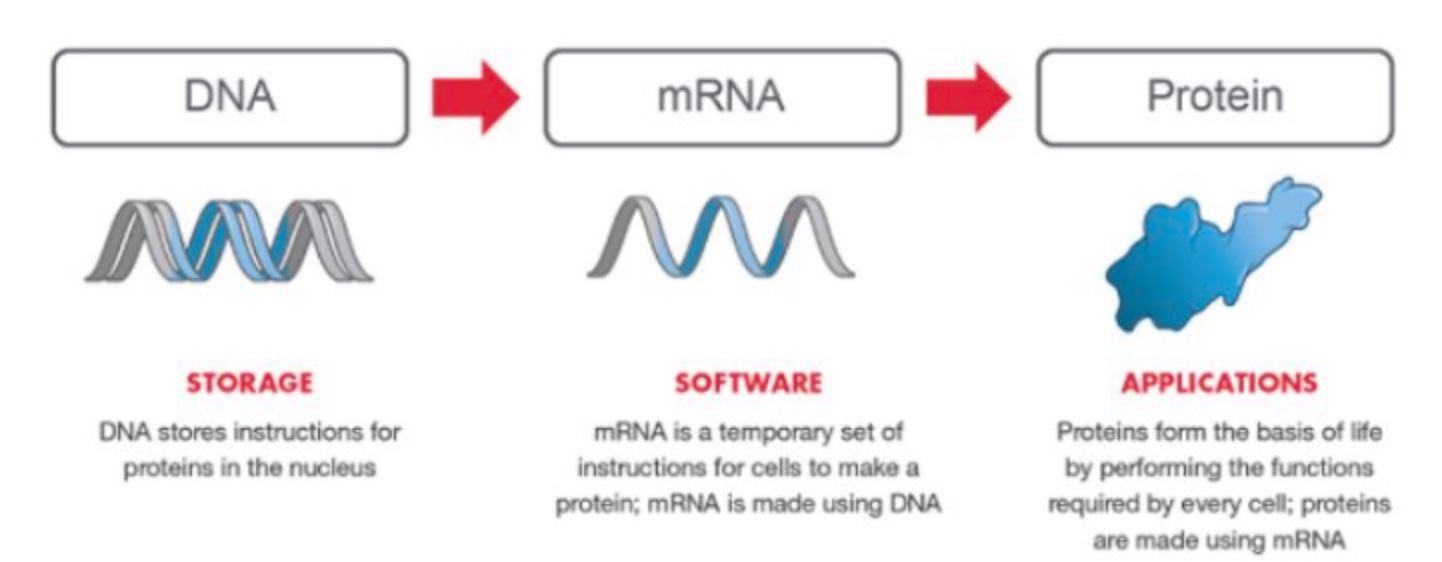

It is capable of fixing design problems in money that no one has thought of yet. How does it do this? The human placentas are filled with 98% HERV viral parts and it routinely consists of a quilt of different genotypes, and this strange heterogeneity plays a role in protecting the fetus from genetic harm. The placenta provides genetic value for the fetus by subtracting our genetic errors for the fetus. Placental evolution is a master idea of the decentralized web Nature provided = its presence is an addition by subtraction.

Nature’s placental innovations rely on spare viral parts and UV light. This is how nature use viruses as a business could use Bitcoin in its operations.

Viruses change bacterial cells/mitochondria/chloroplast and eukaryotic cells massively and they do it quickly. I believe this idea is buried in the evolution of the human placenta. This evolution in mammals began 90 million years ago. Viruses modulate things by changing deuterium fraction in tissues to alter metabolic rates by controling the flow of resources in metabolic pathways.

Dead hosts can still make viral particles and the dead virus can also make more virus using the host to change more hosts. I have a sense that the viral part of the nuclear genome was critical in sculpting the mitochondrial genome to work with the nuclear genome after the Cambrian explosion. I believe this idea had to be worked out first in the placenta before it could be used in fetal development in mammals.

This makes viruses unique in biology, and it also points out why the “enemy of an enemy is often our friend”. All the viral parts in humans really act like ‘dark matter’ capable of harnessing dark energy to innovate solutions to queer environments. The dark matter of the genome is non-coding DNA and RNA and deuterium is its fuel. What ignites this fuel? Full-spectrum sunlight does because of the non-linear effects of UV light on deuterium pulsing in our arteries. This is why young life is affected massively by deuterium levels and why drinking DDW is not always a wise choice in all parts of your life as your heteroplasmy rate vary. You have to know when to use things by understanding the biophysics and biochemistry at the submolecular level. Few do